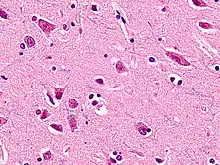

Les neurones en fuseau ou neurones de von Economo (NVE) sont un type de neurones caractérisés par la forme de leur corps cellulaire de grande taille qui est en fuseau s'effilant progressivement en un axone apical unique dans une direction avec seulement un unique arbre dendritique touffu sur le pole basal tourné vers les couches corticales. Les autres neurones ont en effet tendance à avoir de nombreuses dendrites.

Ces cellules neuronales particulières ont été découvertes en 1925 par le neurologue autrichien Constantin von Economo[1],[2]. Les NVE sont de grosses cellules (plus grosses que les cellules pyramidales) fusiformes, avec un axone apical unique et un buisson dentritique sur leur face basale. Ils sont principalement présents dans deux régions cérébrales : l'insula et le cortex cingulaire et un peu plus nombreux dans le cortex cérébral droit[2].